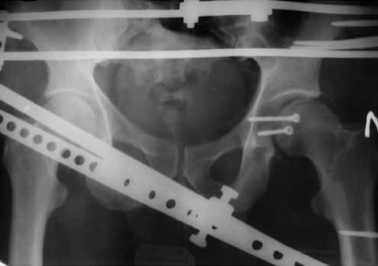

В случае отказа больного от аппарата внешней фиксации или при противопоказаниях производится скелетное вытяжение сроком 3-4 недели. Когда отломок проецируется на уровне или ниже ориентирной линии (рис. 4), разрез производится на 1 см ниже ее. Также тупо разводятся волокна большой ягодичной мышцы.

Рентгенография тазобедренного сустава до и после вправления. Перелом среднего отдела заднего края вертлужной впадины со смещением